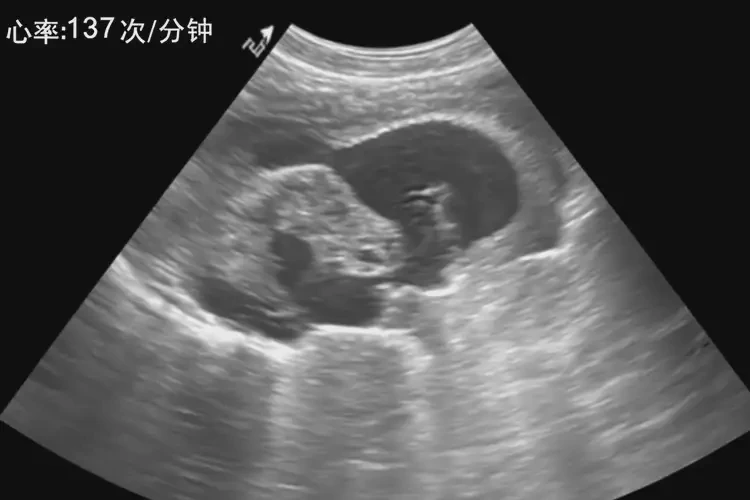

孕27周2天胎心137正常嗎

137次/分鐘

孕27周2天的胎兒心率在137次/分鐘是 正常 的。胎兒心率在孕中期通常在 120-160次/分鐘 之間波動(dòng),137次/分鐘落在這個(gè)范圍內(nèi),表示胎兒心臟功能正常。